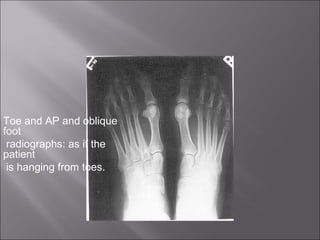

Toe and AP and oblique

foot

radiographs: as if the

patient

is hanging from toes.

Toe and APand oblique foot radiographs: as if the patient is hanging from toes.